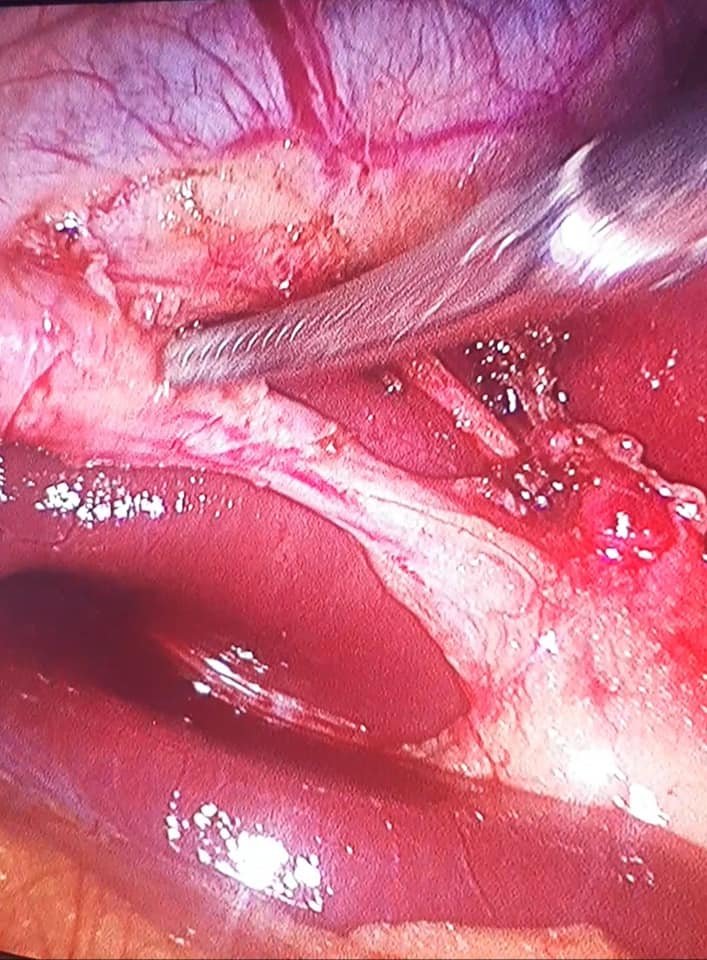

إستئصال المرارة بالمنظار Laparoscopic Cholecystectomy

إستئصال المرارة بالمنظار Laparoscopic Cholecystectomy The Critical View Of Safety (CVS) رابط الفيديو علي الفيس بوك